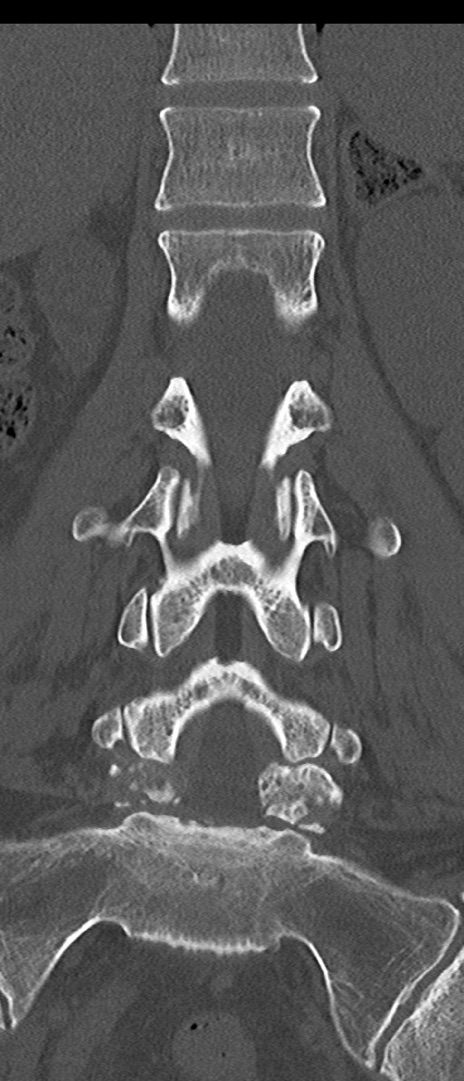

【整形】TIPS症例4 腰椎CT(冠状断像)

腰椎CT